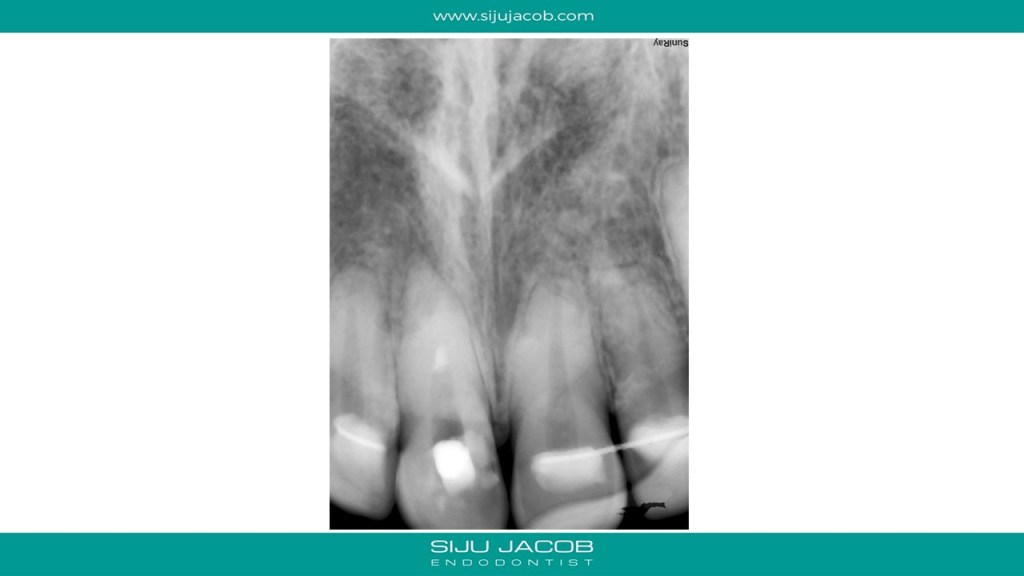

This case was calcified all the way to the apical one third. As we go deeper, the labio-palatal orientation becomes a problem and as we approach the apical part, the margin for error decreases. In this case, I took an inter-appointment CBCT to see the location of the canal. The video explains the whole process.

And here are the pics for the case: